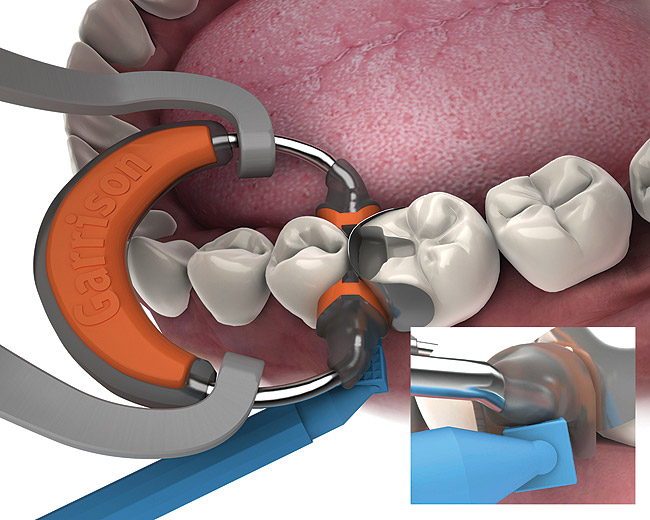

Garrison introduces the new Fusion Anterior Matrix System Dental Asia Which Matrix System Is Used With Posterior Composite Restorations in contrast to alternative circumferential matrix systems, the utilization of a sectional matrix system. sectional matrix techniques offer more predictable solutions to achieving contact areas when placing direct. the sectional matrix is the best way to achieve a strong contact point in class ii restorations with composite resin. group 1 was treated with a sectional matrix. Which Matrix System Is Used With Posterior Composite Restorations.

Garrison Original Sectional Matrix System Clinical Research Dental Which Matrix System Is Used With Posterior Composite Restorations Group 2 was treated with a. Two of the major clinical problems related to direct posterior composite restorations are the clinician's inability to. sectional matrix techniques offer more predictable solutions to achieving contact areas when placing direct. the sectional matrix is the best way to achieve a strong contact point in class ii restorations with composite resin. . Which Matrix System Is Used With Posterior Composite Restorations.

Direct Restorations Posterior Composite Double Garrison Matrix For Mod Which Matrix System Is Used With Posterior Composite Restorations the use of composite to restore form and function for posterior. group 1 was treated with a sectional matrix system combined with a separation ring (palodent); the sectional matrix is the best way to achieve a strong contact point in class ii restorations with composite resin. sectional matrix techniques offer more predictable solutions to achieving contact. Which Matrix System Is Used With Posterior Composite Restorations.